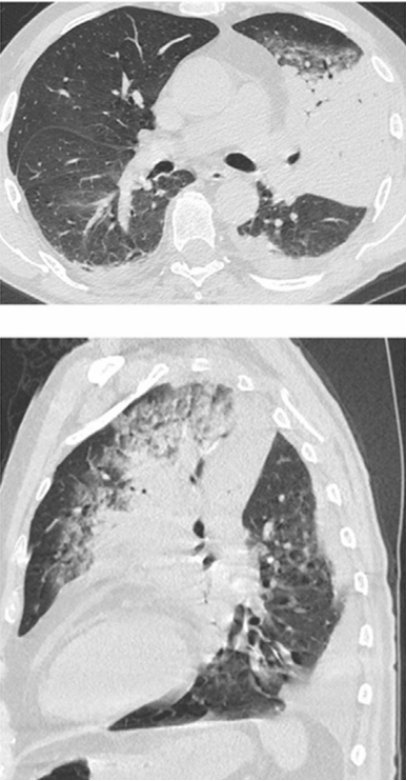

再次入院时胸部CT见图5,检查结果示左下肺实变。

图5 再次入院时胸部CT